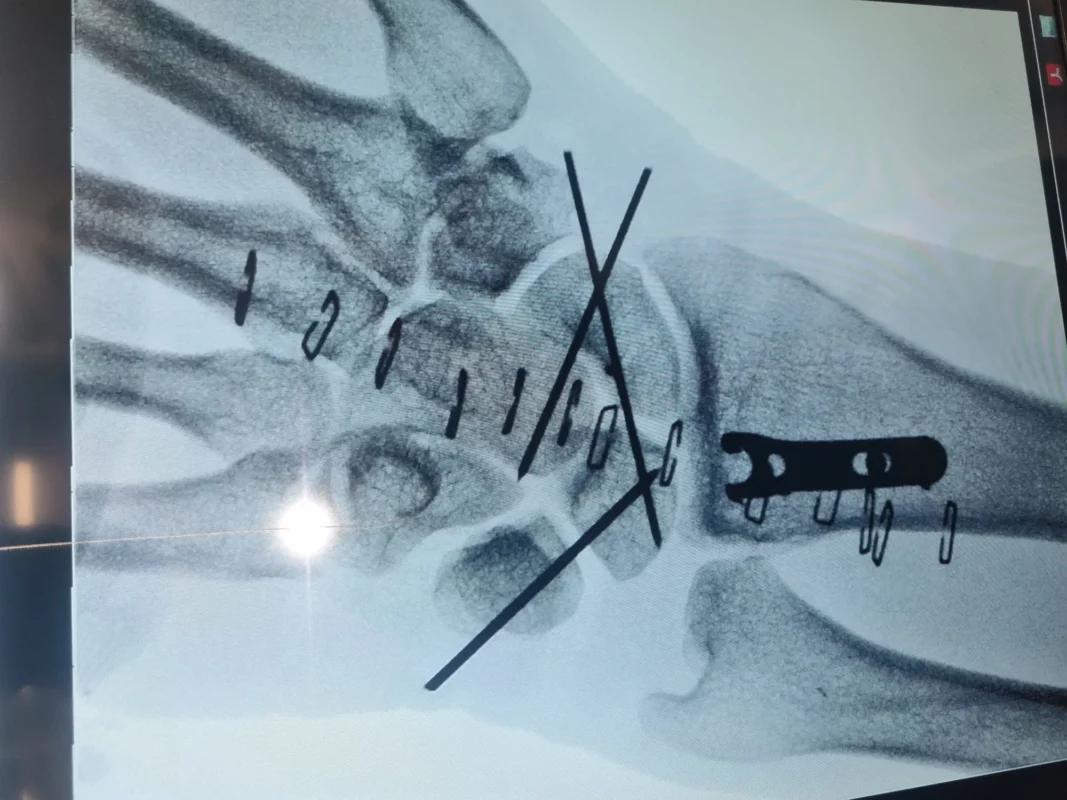

- טיפול ניתוחי: במקרים של שברים מורכבים, ייתכן שיהיה צורך בניתוח להחזרת העצמות למקומן וקיבוע באמצעות פלטות וברגים. ד"ר מאהר חטיב מתמחה בשימוש בטכניקות כירורגיות מתקדמות וחדשניות, כולל ארתרוסקופיה, שהן שיטות זעיר-פולשניות לטיפול בשברים מורכבים. שיטות אלה מאפשרות התאוששות מהירה יותר, הפחתת סיבוכים ושיקום יעיל.